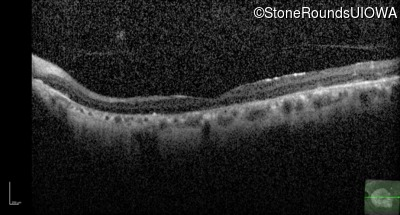

OCT Stack